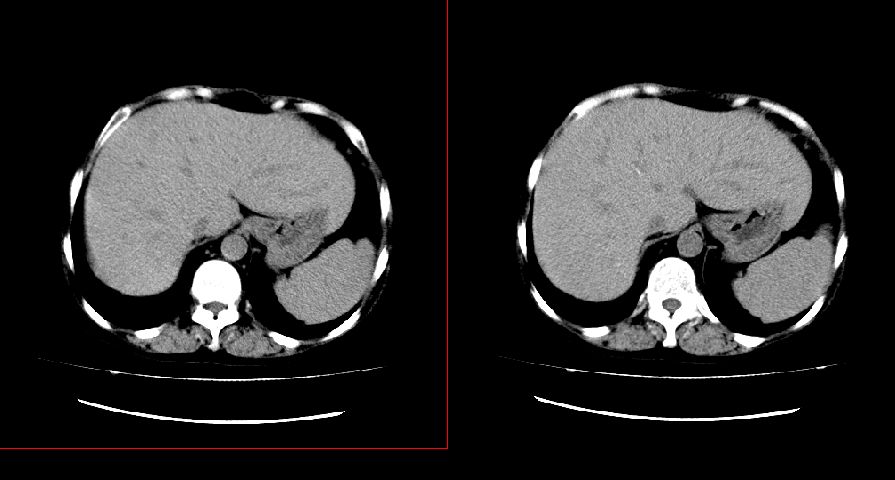

以下是引用liuyue在2008-7-19 10:17:00的发言:[br]考虑:1.肾周脓肿,肾实质、腰大肌及侧腹壁均受累及。 2.右肾囊肿。[br]建议:强化扫描,除外肾癌之可能。[br]

以下是引用zhengfaming在2008-7-19 14:48:00的发言:[br]右肾脓肿并感染可能性大,建议增强

以下是引用江广1996在2008-7-19 10:48:00的发言:[br]先考虑右侧肾周感染脓肿形成并累及腰大肌,右肾前侧有病灶考虑囊肿。